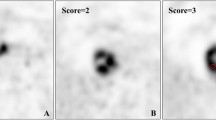

The standardised uptake value (SUV) from 18F-FDG PET/CT is a dimensionless ratio used to distinguish between normal and abnormal levels of glucose uptake and can be considered an image-derived semi-quantitative parameter, defined as the ratio activity per unit volume of a ROI to the activity per unit whole-body volume (Figs. 5 and 6) [19].

18F-FDG PET/CT scan of a 72-year-old man with gastro-oesophageal junction cancer (a–d) demonstrated by an intense uptake of 18F-FDG before treatment (SUVmax = 10.7) (c). After two cycles of chemotherapy (paclitaxel + cisplatin + fluorouracil) (e–h), the SUVmax of the lesion decreased to 4.8 (g), showing good response to the therapy. Final pathology (i) ypT3N0 (tumour regression grade 1)

18F-FDG PET/CT scan of a 48-year-old woman with gastric cancer (a–d) demonstrated by an intense uptake of 18F-FDG before treatment (SUVmax = 4.7) (c). After one cycle of chemotherapy (capecitabine + paclitaxel) (e–h), no significant changes in 18F-FDG uptake (SUVmax = 4.8) were observed (g). Final pathology (i) ypT4aN1 (tumour regression grade 3)